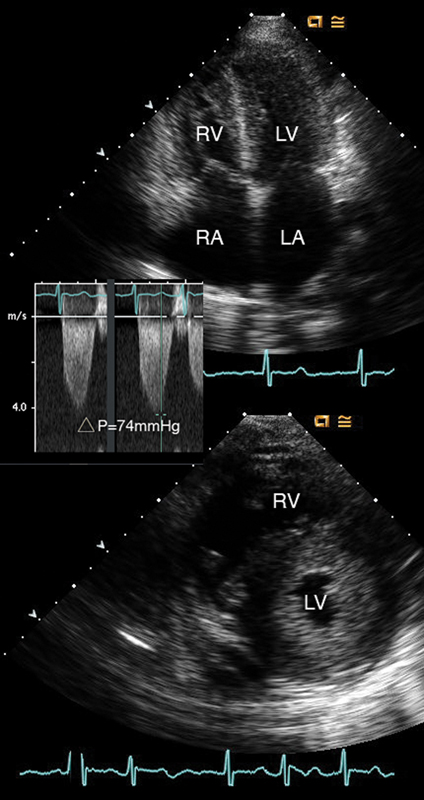

فحوصات تشخيصية لبعض امراض القلب والشرايين التاجية